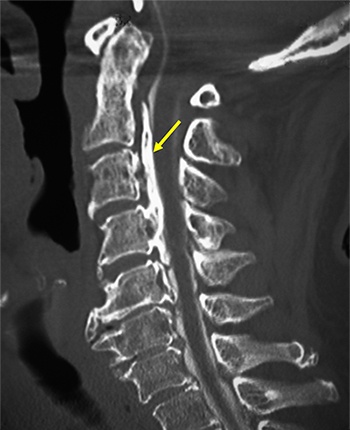

図1 後縦靭帯骨化症(OPLL)患者のCT画像

頸椎(首の部分)の側面から見たCT画像。矢印は骨化した後縦靭帯。